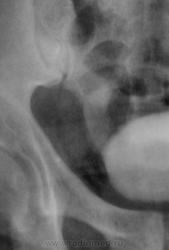

Признавайтесь, куда делась средняя треть правого мочеточника? Ее как-будто ножом отрезали под линейку, а ниже-сплошное безобразие! "ЧТО" может как обезобразить орган-банальная МКБ с частичной обтурацией просвета или опухоль? А в пузыре тоже камни?

А деформация мочевого пузыря никого не смущает?

Отчего же не смущает?))) смущает...она и есть первопричиной образования ТАКОГО камня в мочеточнике, теперь об этом можно сказать с уверенностью, ее генез - выраженое увеличение размеров простаты.

С простатой при отсутствии УЗИ достаточно пальцевого осмотра хирургом до экскреторного исследования. Если простата не увеличена пальпаторно, то получив такую картинку мочевого пузыря на первых минутах после введения контраста, я бы сделал косые снимки мочевого пузыря (заодно и тень в н/3 правого мочеточника покрутить).